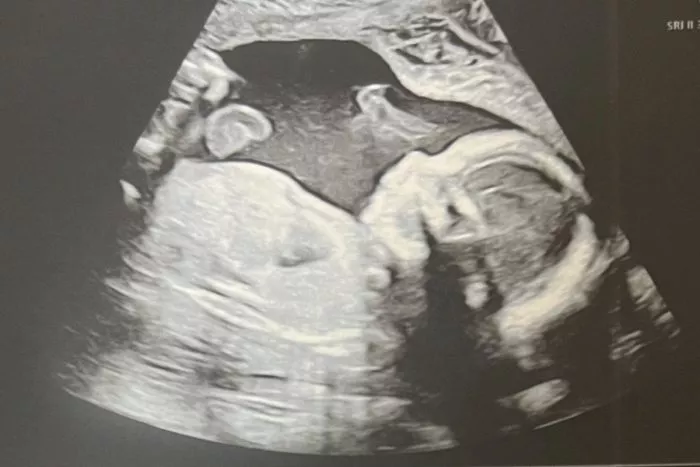

Budeme mít syna 👶

V dubnu 2024 očekáváme narození syna. Ten nejlepší moment mého dosavadního života, o kterém jsem psal výše? Když jsem ho viděl poprvé na živém ultrazvuku. 😊

Úplně se mi obrátil svět a strach ze smrti téměř zmizel. Najednou mi přijde, že toho máme tolik před sebou! Chci být úplně u všeho a naplno využiju toho, že můžeme pracovat z domova. V kanceláři mě nejspíš uvidí mnohem méně než doteď, ale první měsíce (a roky) života našeho dítěte si rozhodně nenechám ujít.